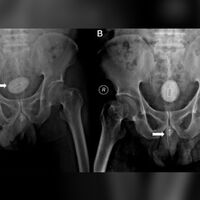

У мужчины из Индонезии удалили из уретры инструмент для извлечения SIM-карты, электрический кабель и канцелярскую резинку. Об этом сообщает Daily Mail.

48-летний мужчина из Индонезии обратился к врачам из-за боли и нарушения мочеиспускания. Пациент шесть месяцев прожил с инородными предметами в уретре. Анализы крови и мочи показали, что у мужчины была почечная недостаточность и инфекция мочевыводящих путей.

Металлический инструмент для извлечения SIM-карт привел к образованию камня в мочевом пузыре и сильной боли. Его, а также электрический кабель длиной 10 см и иглу длиной 8 см, перевязанную резинкой, удалили хирурги.

Мужчина смог нормально мочиться через неделю после процедуры. Через шесть недель у него не было никаких осложнений, а функция почек оказалась нормальной.